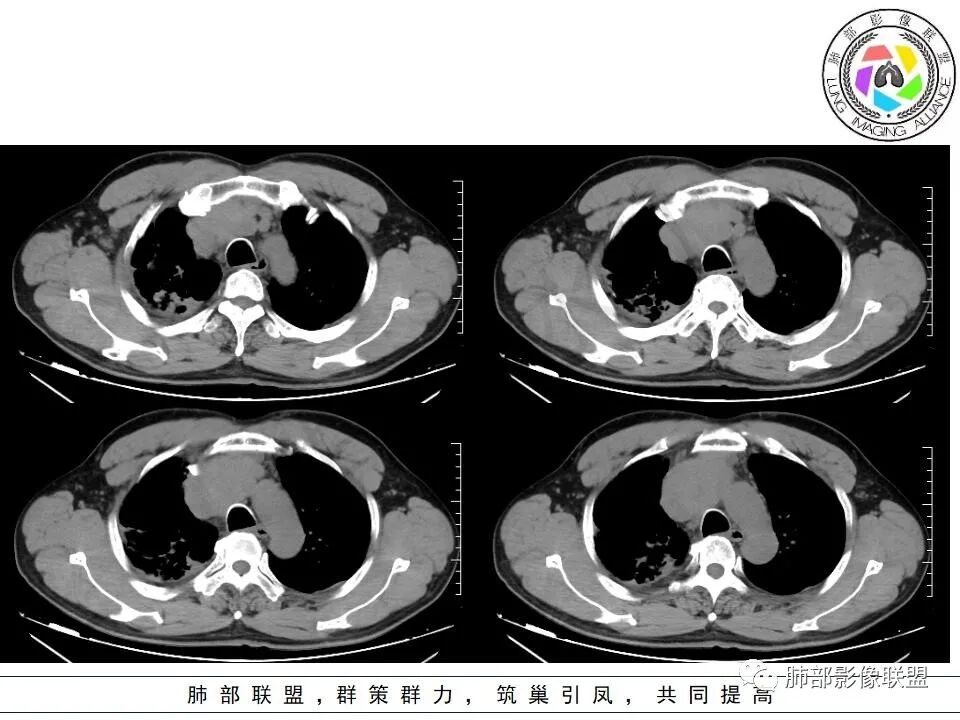

老年,前纵隔实性占位,中心生长,轻中度强化,少许坏死,侵犯上腔、无名静脉。

考虑恶性:胸腺癌>高危胸腺瘤

直接侵犯上腔、无名静脉大血管,淋巴瘤和胸腺瘤的可能性都比较小,更多见于胸腺癌

晨读,老年男性,面部肿胀1月余。前纵隔肿块,边缘膨隆,见分叶,整体较均匀强化,内见小坏死,侵犯周围大血管,考虑恶性,胸腺癌可能性大。

●老年男性

●前纵隔占位明确

●上腔静脉侵犯明确

●定性恶性明确

综合分析:

1.面部肿胀的临床表现很难让我们不联想到胸部的恶性肿瘤,如肺癌对纵隔的侵犯。

2.右肺上叶病灶,纤维硬结灶及支扩等,应该存在时间较长。

3.影像表现不复杂,上纵隔胸腺所在区域边界不清肿块影且侵入上腔静脉及左无名静脉等,具有较明显的恶性生物学行为。

4.综合分析更符合胸腺癌肿,原发可能性较大。

5.病理报告B2胸腺瘤出乎意料,应当囿于取材限制,而非手术大体病理。